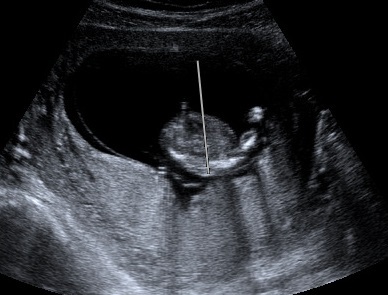

Attachment 19527Attachment 19528At my NT scan at 13 weeks (baby measured 14 weeks 1 day) the tech said if she had to bet she would say it is a girl. Yesterday I had a scan at 16 weeks(not sure where baby is measuring) with my ob he said he's not an expert but that he agrees with the tech that baby is a girl and that we can tell family just not announce on facebook(not a problem for me :) ). I'm still nervous that our little girl is actually a boy that's why I would love some more opinions/guesses from you all. Thanks!